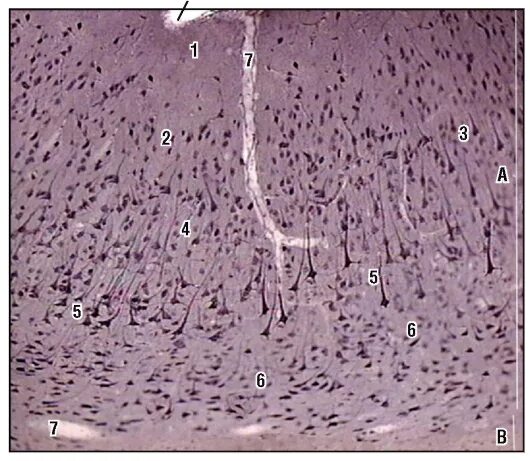

Гистология головного мозга